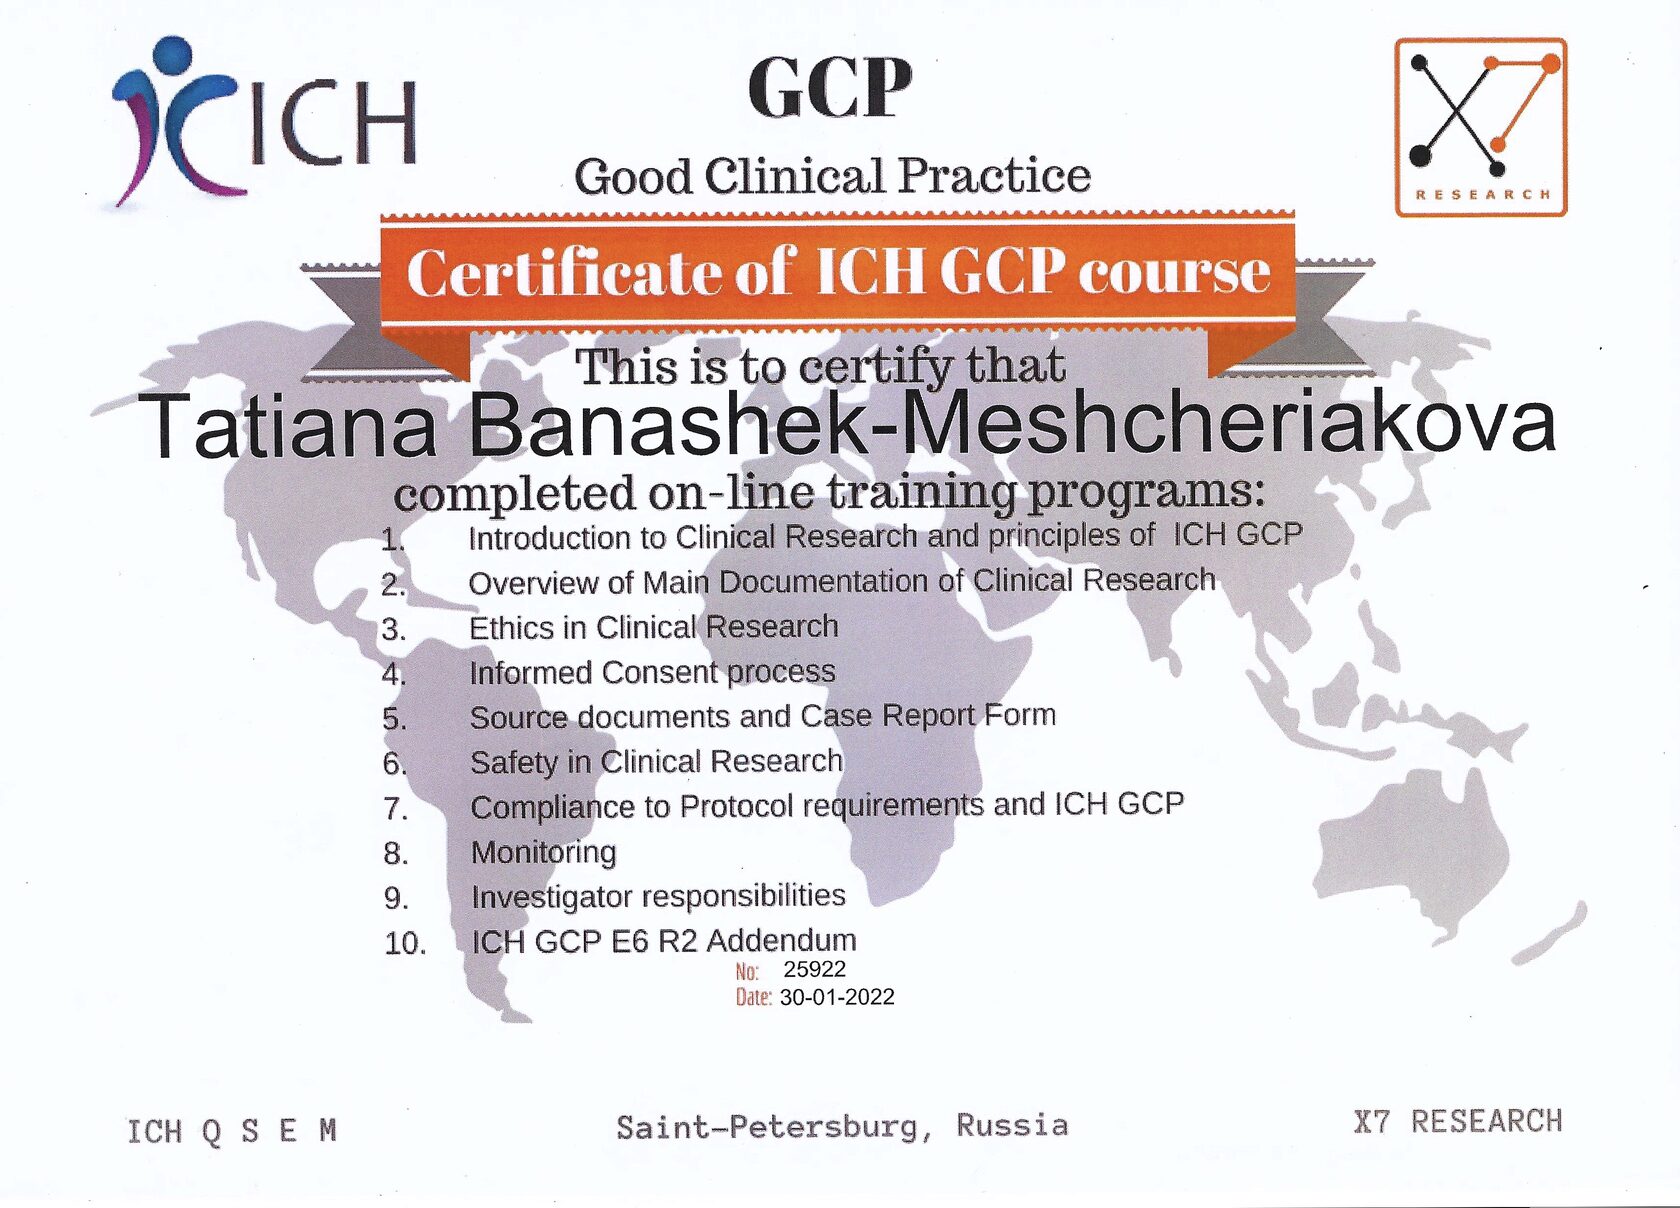

Грамоты